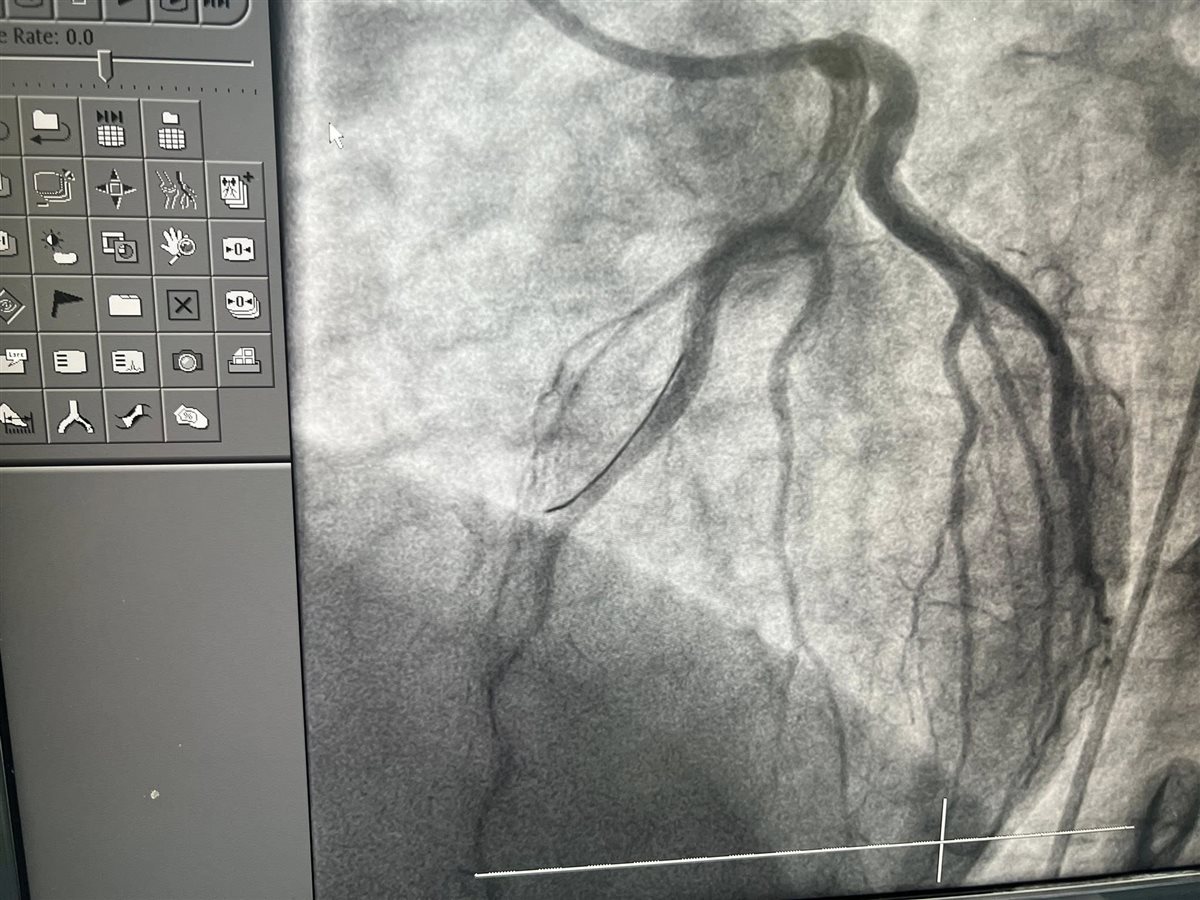

وقال في منشور له عبر حسابه على موقع التواصل الاجتماعي فيس بوك مرفقا بعدد من الصور للفحوصات الخطيرة للشباب: خلال ثلاثة أيام فقط من عيد الأضحى، استقبلنا بالمستشفى 13 حالة طوارئ مصابة بجلطات حادة في القلب، وجميعها من فئة الشباب الذين لا يعانون من أي أمراض مزمنة أو عوامل خطر تقليدية كارتفاع ضغط الدم أو مرض السكري، والعامل المشترك الوحيد بينهم كان تعاطي الحشيش.

وتابع حلمي راصدًا حجم المعاناة: كما استقبلنا شابًا يبلغ من العمر 28 عامًا، لا يعاني من أي أمراض مزمنة، لكنه أصيب بجلطة حادة بالقلب وكان الشريان التاجي في حالة سيئة جدًا لا تتناسب مع سنه، وفي حالة أخرى، شاب في الثانية والثلاثين من عمره خرج من مستشفى بعد فحص أولي طبيعي، لكن مع أول رسم قلب عندنا ظهر ارتفاع ST واضح، وتبين في القسطرة أن الشريان التاجي الأمامي النازل كان غير ظاهر تمامًا، وكدنا نظن أنه غير موجود، لكننا بفضل الله وبتعاون فريق القلب في المستشفى استطعنا تحديده وتوسيعه وتركيب دعامة لإنقاذ حياته.